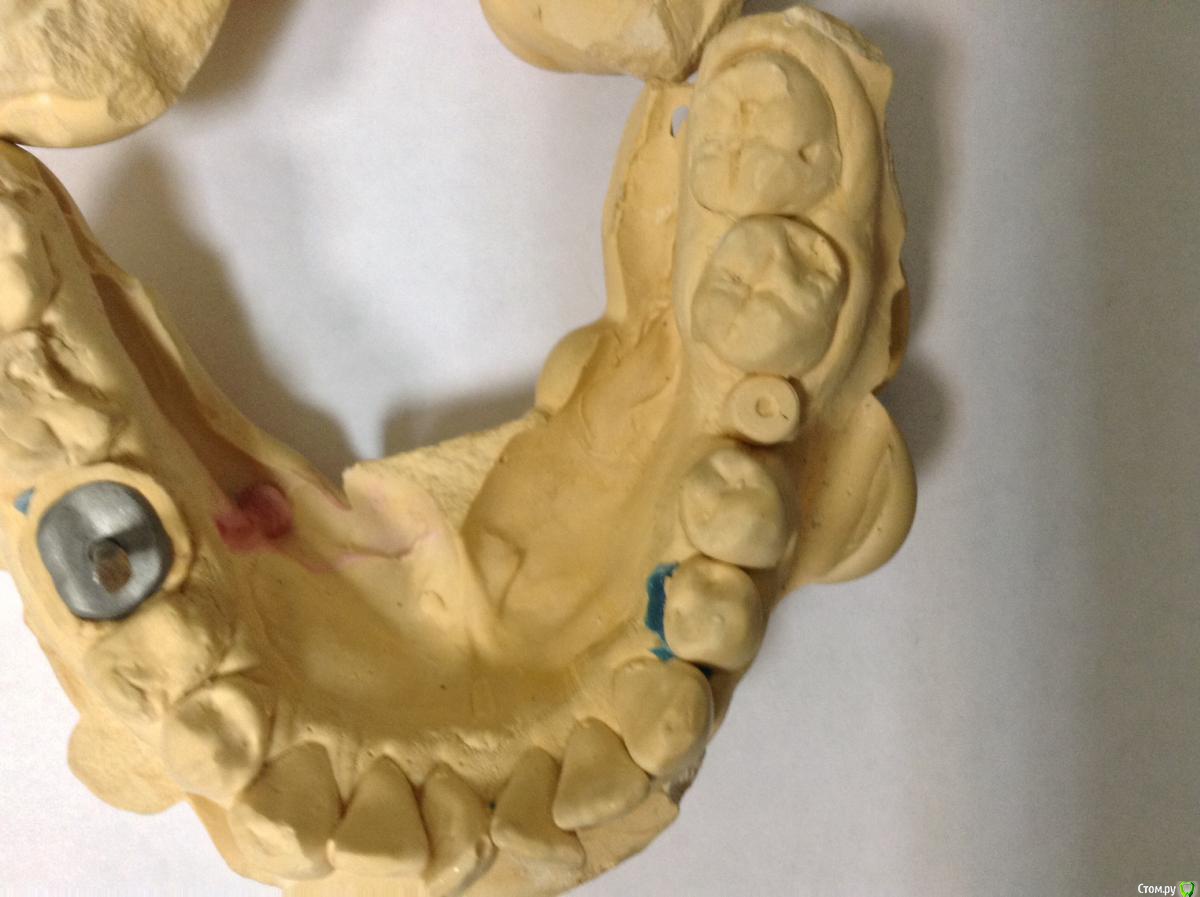

ksenistom Опубликовано 2 декабря, 2014 Поделиться Опубликовано 2 декабря, 2014 Уважаемые коллеги,подскажите пожалуйста,как быть в данной клинической ситуации? Ссылка на комментарий

Aquarius Опубликовано 2 декабря, 2014 Поделиться Опубликовано 2 декабря, 2014 Почему места недостаточно?)) Все получится, даже у среднеграмотного техника. Где одиночка, премолярчик выйдет) Ссылка на комментарий

ksenistom Опубликовано 2 декабря, 2014 Автор Поделиться Опубликовано 2 декабря, 2014 1,5мм ширина костной перегородки для формирования сосочка,а конструктивно(для техника) разницы нет.То есть в данной ситуации достаточно места для протезирования? Ссылка на комментарий

chernov Опубликовано 2 декабря, 2014 Поделиться Опубликовано 2 декабря, 2014 (изменено) То есть в данной ситуации достаточно места для протезирования?в технической части-да,достаточно,а с эстетикой могут возникнуть проблемы. Изменено 2 декабря, 2014 пользователем chernov Ссылка на комментарий

togrul Опубликовано 2 декабря, 2014 Поделиться Опубликовано 2 декабря, 2014 В данной ситуации лучше сделать на стандартных абатментах , места мало между имплантатами гигиена будет страдать. Ссылка на комментарий

Евгений Ходыкин Опубликовано 3 декабря, 2014 Поделиться Опубликовано 3 декабря, 2014 Делайте в блоке премоляры, техники размоделировать смогут. Про эстетику забыть... Ссылка на комментарий

ksenistom Опубликовано 3 декабря, 2014 Автор Поделиться Опубликовано 3 декабря, 2014 Делайте в блоке премоляры, техники размоделировать смогут. Про эстетику забыть...Премоляры я поняла,что в блоке,спасибо))а что делать с одиночкой? Ссылка на комментарий

chernov Опубликовано 4 декабря, 2014 Поделиться Опубликовано 4 декабря, 2014 одиночку! 1 Ссылка на комментарий

Евгений Ходыкин Опубликовано 4 декабря, 2014 Поделиться Опубликовано 4 декабря, 2014 Премоляры я поняла,что в блоке,спасибо))а что делать с одиночкой?Не ахти какую, но делайте)) Ссылка на комментарий